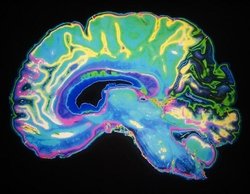

عامل مختل کننده حافظه و یادگیری

بر اساس تحقیقات دانشگاه لستر انگلستان مشخص شد چه عاملی عملکردهای شناختی مانند حافظه و یادگیری را با افزایش سن دچار اختلال میکند.

بر اساس تحقیقات دانشگاه لستر انگلستان مشخص شد چه عاملی عملکردهای شناختی مانند حافظه و یادگیری را با افزایش سن دچار اختلال میکند. به گزارش آوای نشاط، نتایج این تحقیقات نشان میدهد که میزان کلسیم، نقش مهمی در عملکرد سلولهای خاص در مغز دارد.

پروفسور نیک هارتل از گروه علوم اعصاب- روانشناسی و رفتار دانشگاه لستر میزان کلسیم موجود در هیپوکامپ، بخشی از مغز که در یادگیری و حافظه درگیر است را مورد بررسی قرار داد.